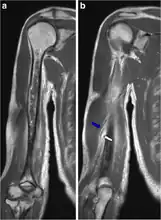

Chest X-ray pneumonia

CT pneumonia

X-ray pneumococcal osteomyelitis

MRI pneumococcal osteomyelitis